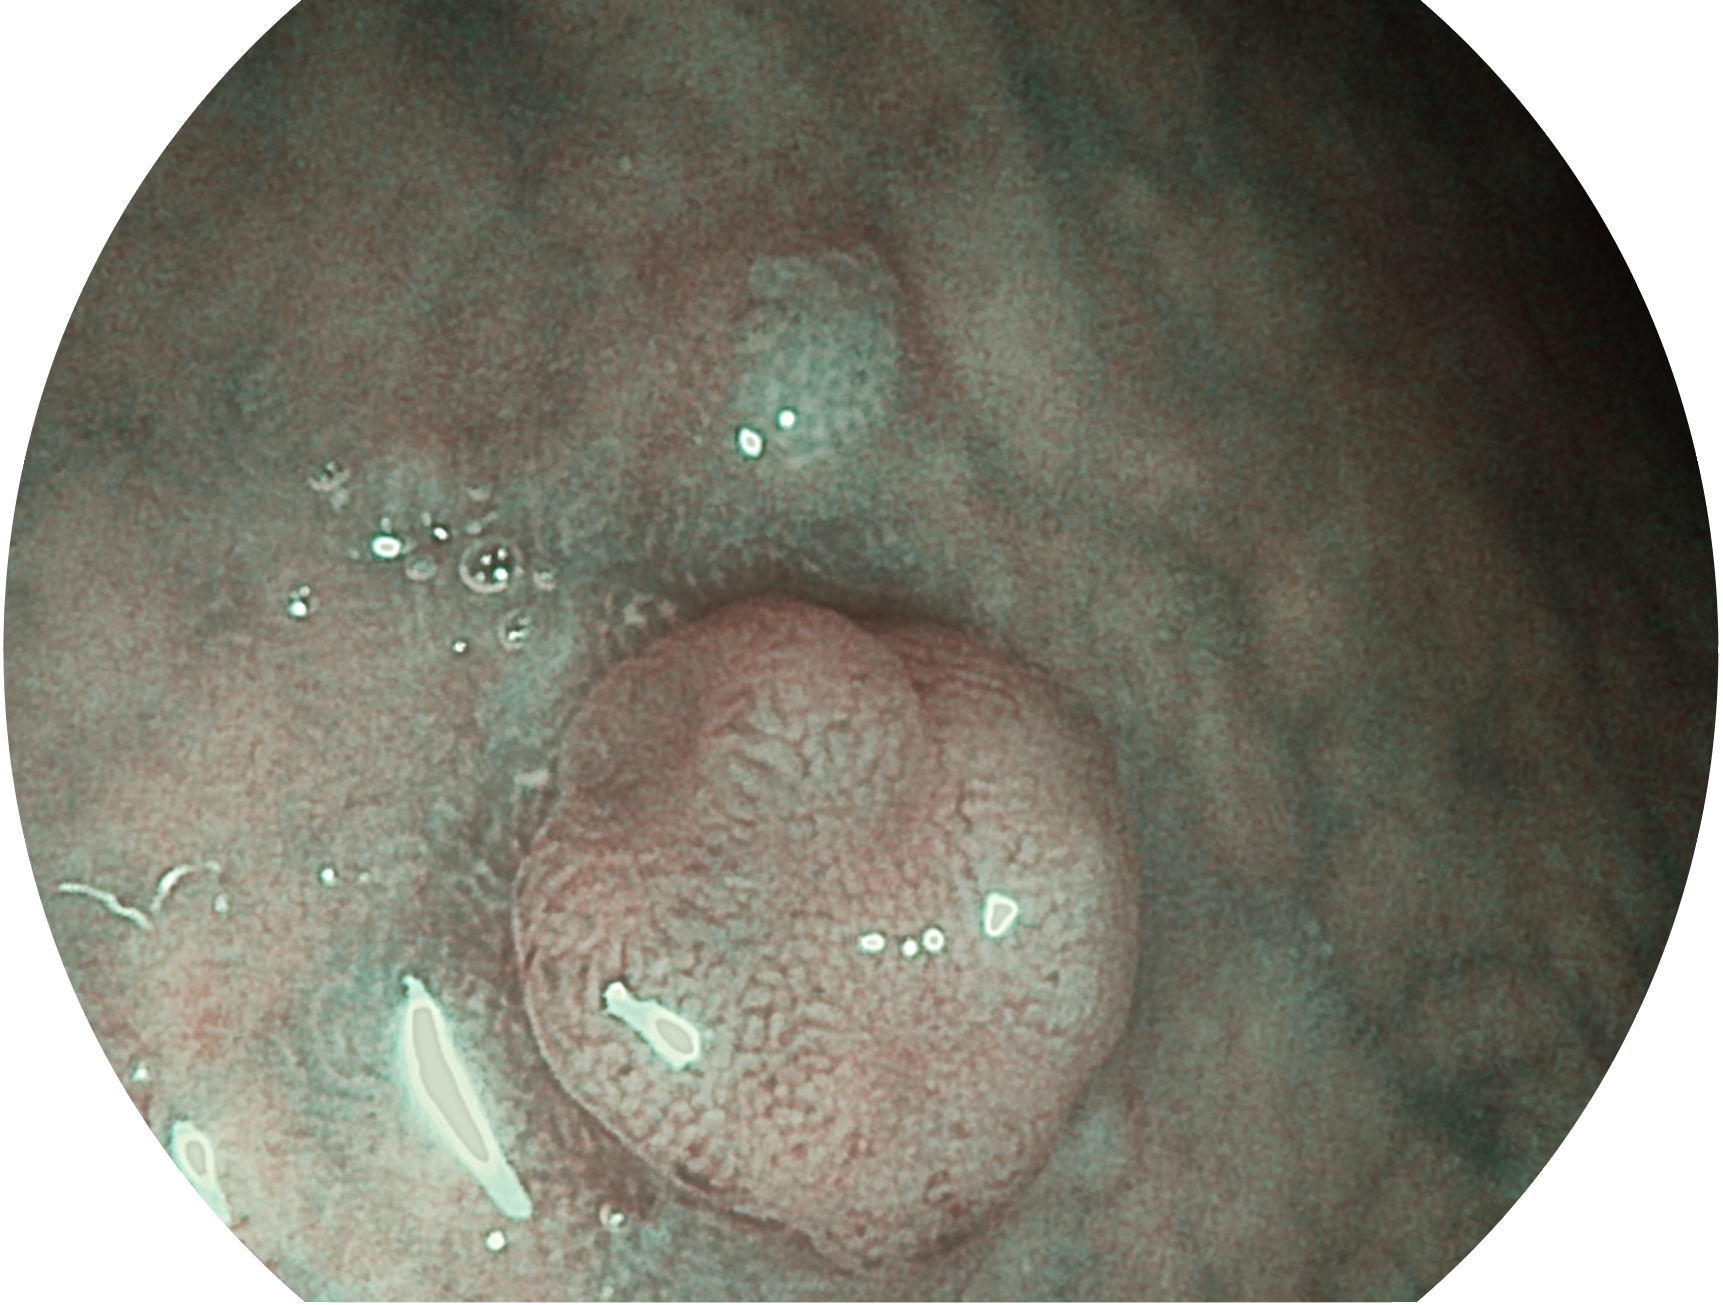

DB中国旗舰官方网站新开发的内镜染色技术,主要是基于多波长LED 光源的开发,VLS-55Q 四波长LED 光源是由四个不同颜色的LED光按照相应照明模式所规定的特定发光比例进行合束后形成,合束后形成的照明光的光谱由红光、绿光、蓝光及蓝紫光这四个不同的波段范围构成。具有更高光谱自由度,通过光谱比例的控制,实现了聚谱成像技术,英文全称为“Spectral Focused Imaging, SFI”,缩写为“SFI”和光电复合染色成像技术,英文全称为“Versatile Intelligent Staining Technology, VIST”,缩写为“VIST”。